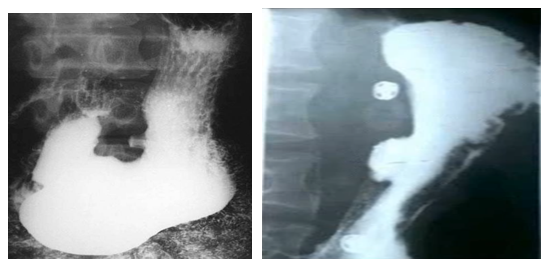

男性,55歲,上腹隱痛約十年,請(qǐng)做出正確診斷

A.胃癌

B.胃潰瘍

C.十二指腸潰瘍

D.食管癌

E.胃憩室

【答案】B